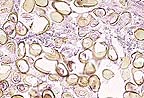

Numerous intrahistiocytic cytoplasmic inclusions in the bursa of a racing pigeon with avian cercoviral infection. (HE, 400X, 6K)

Contributor's Diagnosis and Comments: Moderate diffuse lymphoid necrosis and depletion, bursa of Fabricius. Acute bursal abscessation.

Lymphoid depletion was also evident in the spleen. The cause of death was considered secondary bacterial infection associated with an immunocompromised state. Although no additional diagnostic tests were performed, the presence of characteristic intracytoplasmic inclusions bodies was considered to be consistent with circovirus infection.

AFIP Diagnosis: Bursa of Fabricius: Lymphoid depletion, diffuse, severe, with lymphocyte necrosis and intrahistiocytic basophilic intracytoplasmic inclusion bodies, pigeon, avian.

Conference Note: Circoviruses are a newly proposed group of circular, single-stranded DNA viruses. The circoviruses of pigeons, psittacine beak and feather disease virus, chicken anemia agent, and nonpathogenic porcine circovirus share similar ultrastructural characteristics, protein composition, and antigenic features.

Pigeons with circoviral infections develop lesions in the spleen, bursa of Fabricius, gut-associated lymphoid tissue, and bronchus-associated lymphoid tissue. Changes in the spleen can range from lymphofollicular hyperplasia with mild lymphocyte necrosis to lymphoid depletion and histiocytosis. Bursal changes can also range from mild lymphocyte necrosis to severe cystic bursal atrophy. Basophilic intracytoplasmic inclusion bodies can be seen in macrophages in splenic, bursal, gut-associated, and bronchus-associated lymphoid tissue and in bursal epithelial cells. Ultrastructurally, the virus appears in paracrystalline arrays of tightly packed, nonenveloped icosahedral virions 14-17 nm in diameter. Many circovirus infections in pigeons are complicated by secondary bacterial or viral disease, probably as a result of some degree of immunosuppression secondary to viral infection of the monocyte-macrophage system.